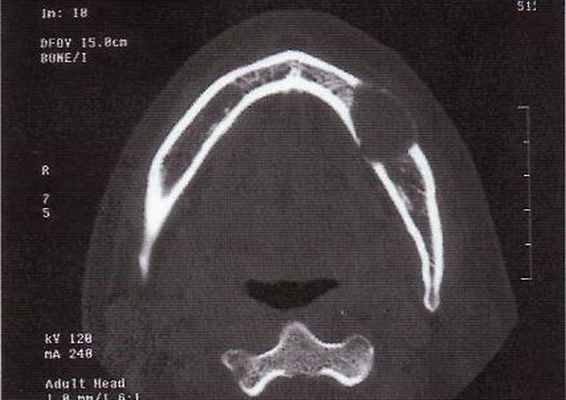

Одонтоамелобластома очень редкая опухоль, состоящая из форм амелобластомы, сочв сочетании с отложениями дентина и эмали, которые иногда напоминают зачаток зуба. Обладает, как и амелобластома, местно деструирующим ростом.

Рентгенологически определяется узловатое плотное образование, окаймленное светлой четкой полосой.

Макроскопически многообразна от небольших образований, напоминающих недоразвитый или деформированный зуб, до массивных конгломератов, состоящих из нескольких зубоподобных образований, легко разделяющихся или плотно спаянных; окружена капсулой. Иногда содержит кисты, заполненные светлой жидкостью.